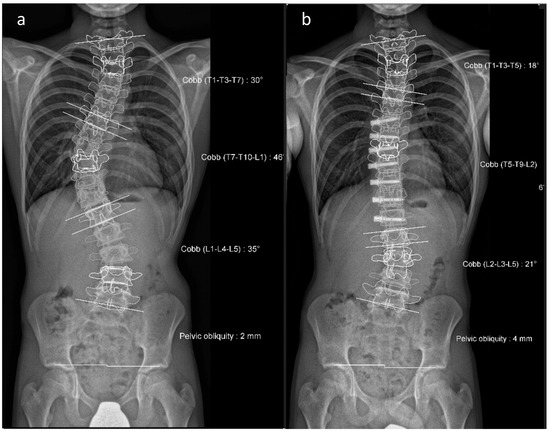

Figure 5. (a,b). Initial radiographs of a patient with adolescent idiopathic scoliosis. (c,d). Bending radiographs. (e,f). Postoperative image displaying implanted magnetically controlled growing rods as a dual rod system. (g,h). The patient was treated with a spondylodesis upon the completion of growth to maintain correction success (Reprinted with permission [10]).

To avoid the regular surgical lengthening procedure, MCGRs were developed and approved for the treatment of EOS in Europe in 2009. MCGRs are telescopically extendable distraction rods. They can be distracted non-invasively, on an outpatient basis, by externally magnetically controlled lengthening using electromagnets. Figure 5 illustrates the progression of treatment for a patient with AIS, starting from initial diagnosis, through the bending radiographs, to the postoperative phase with implanted MCGR, and finally, the maintenance phase involving spondylodesis.